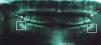

CASE REPORTDuring clinical evaluation, the patient reported as reason for consultation «I have crooked teeth». In the initial radiographic studies, the lateral head film showed normodivergency and a mild proclination of the upper and lower incisors (Figure 1). In the panoramic radiograph no pathological data were noted; the patient had 28 permanent teeth, formation of the lower third molars and agenesis of the upper (Figure 2).